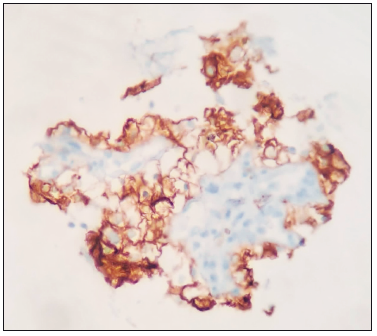

La biopsia guiada por USE fue complementada con una evaluación citológica rápida onsite (ROSE), la cual mostró citología positiva para malignidad en el primer pase. Posteriormente, la histopatología diferida confirmó células claras con inmunohistoquímica positiva para PAX8 y CD10, consistente con metástasis de CCCR (Figuras 3 y 4).

Figura 3. Fragmento de biopsia de lesión mesorrectal con tinción CD10 de membranas

compatible con células claras renales

Figura 4. Fragmento de biopsia de lesión mesorrectal con tinción PAX8 de núcleos